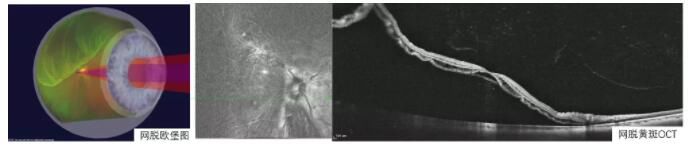

文章插图

(网脱欧堡图和网脱黄斑OCT图)

这个时候应该立即就诊,早发现,早治疗,否则视功能损害将不可逆转,多数情况下需要尽早通过视网膜复位手术才能解决。